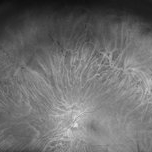

Fundus auto-fluorescence of a 41 year old female depicting retinal pigment epitheliopathy and exudative retinal detachment in case of ocular metastasis secondary to breast carcinoma.

Photographer: Dr.Rabia Naaz, National Institute of ophthalmology, Pune

Imaging device: OPTOS DAYTONA

Condition/keywords: Exudative retinal detachment, Retinal pigment epitheliopathy